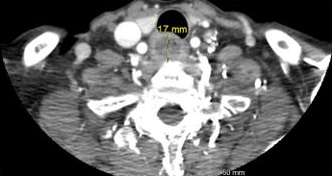

Figure 1. Sagittal and transverse views of esophageal food bolus impaction

Laboratory tests—including complete blood count, basic metabolic panel, liver panel, and lipase—were within normal limits. A chest X-ray revealed no radiopaque foreign bodies. A contrast-enhanced computed tomography (CT) scan of the neck and chest identified a 3.0 × 1.2 × 1.7 cm food bolus (Figure 1) lodged at the C6–C7 level, adjacent to an anterior C6–C7 osteophyte (Figure 2).